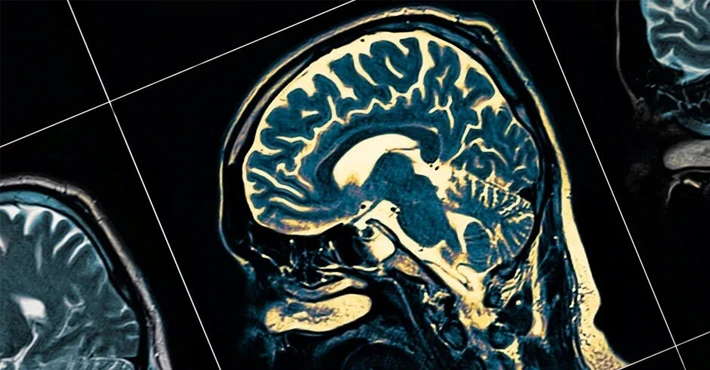

Genetik ve değiştirilebilir risk faktörlerinin yaşlanma ve hastalıklara karşı savunmasız beyin bölgeleri üzerindeki etkileri araştırıldı. Çalışma kapsamında 45 yaş üstü 40 bin katılımcının beyin MR’ları incelendi.